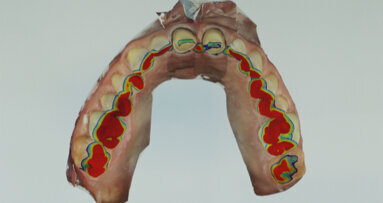

Úspěšné endodontické ošetření závisí na řadě faktorů, včetně správné instrumentace, úspěšné irigace a dekontaminace systému kořenových kanálků včetně apikálního zakončení a špatně přístupných oblastí jako jsou zúžení a postranní a vedlejší kanálky (obr. 1a, 1b).

Z hlediska úspěšnosti endodontického ošetření vždy bylo problémem odstranění vitálních a nekrotických zbytků dřeňových tkání, detritu vznikajícího při instrumentaci, smear layer, mikroorganizmů a mikrotoxinů ze systému kořenových kanálků. Je obecně známo, že i při použití rotačních nástrojů působí současné nikltitanové nástroje pouze na centrální část kořenového kanálku, což vede k nutnosti irigace, která vyčistí to, co po těchto nástrojích zbyde.

Tvarováním kanálků vzniká dostatek prostoru fungujícího jako účinný zásobník irigačního roztoku, který může po aktivaci pronikat, cirkulovat a likvidovat tkáně z neopracovaných částí systému kořenových kanálků.“